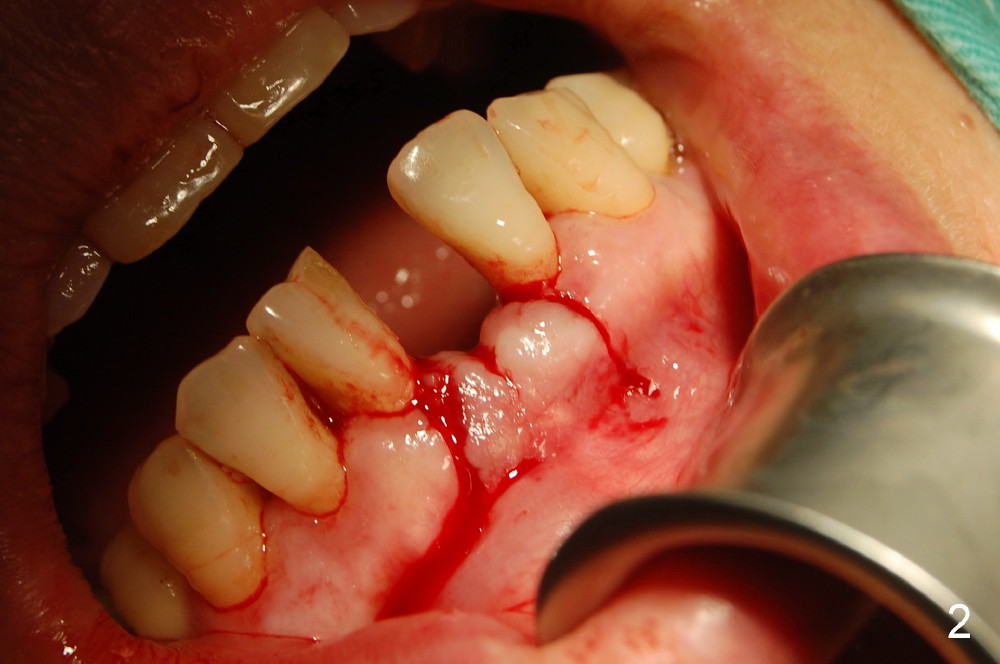

2,左下1舌侧附着龈切口,翻开唇侧粘骨膜瓣,测量牙槽嵴唇舌侧厚度仅4mm,唇侧牙槽嵴下方明显凹陷,约厚3.5mm。证实了术前预估的骨量情况,如孔道唇侧侧壁穿孔就植骨粉,已和病人交待。

为了提高种植体的稳定性,钻孔时小心翼翼,长轴的近远中特别是唇舌侧角度一点都不敢大意,只打了两钻,非常幸运没有侧穿!!但孔道侧壁骨壁可透光,住院医的手术记录为”薄如蝉翼“,”妙“。(终于没白教她们,懂得了体会其难度)

不敢打第三钻了,改为攻丝,植入3.3x12mm骨水平美学种植体,透过骨壁种植体清晰可见。

所以,还是在唇侧骨面上种植体的两旁各打了几个小眼使其出血,植入Bioss骨粉,上覆盖Biosmate骨膜,减张包埋缝合。